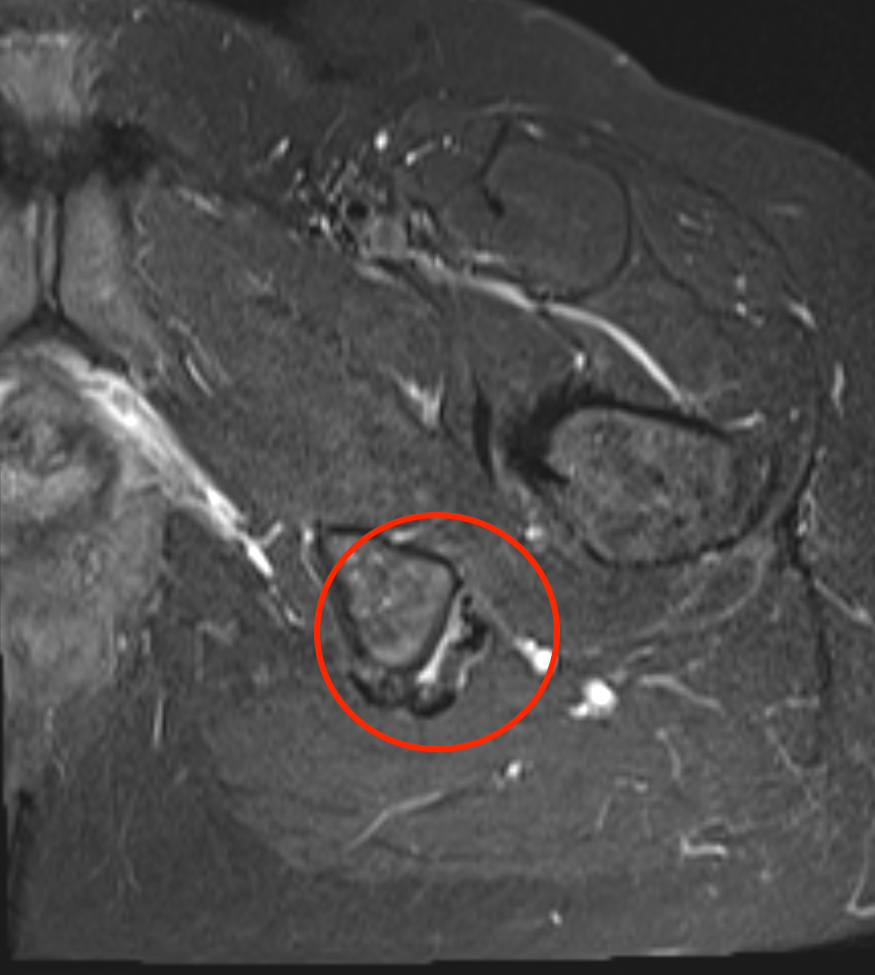

Identify sciatic nerve lateral and semimembranosus tendon medial to conjoint muscle belly and tendon

Divide semimembranosus tendon and suture to conjoint tendon (star - sciatic nerve, # - conjoint tendon)